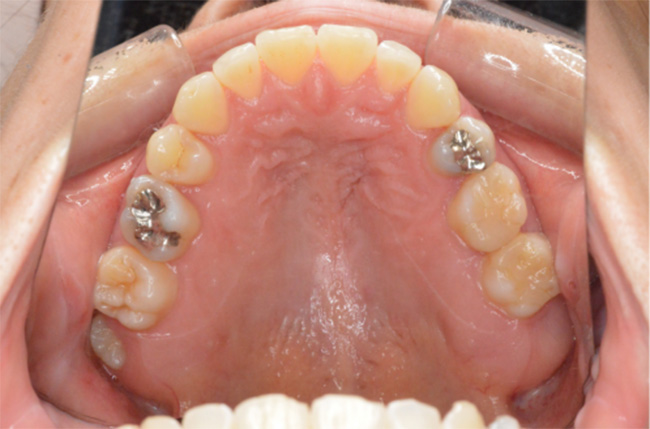

治療終了時

| 治療方法 | 上下顎小臼歯4本抜歯、ワイヤー矯正 |

| 治療内容 | 抜歯のスペースを使用して、上下前歯を後退させた |